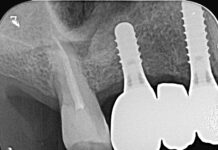

Lo studio è stato impostato secondo un modello split-mouth, cosicché sono stati reclutati pazienti indirizzati a estrazioni di coppie di elementi con morfologie radicolari simili sui due lati opposti del mascellare superiore o della mandibola.

Sono state raccolte misurazioni dello spessore crestale (clinicamente) e dell’altezza ossea apico-coronale (radiograficamente) al baseline, a 3 mesi e, infine, a 6 mesi. Solo quest’ultima è risultata significativamente superiore rispetto ai controlli non innestati, sia a 3 che a 6 mesi.